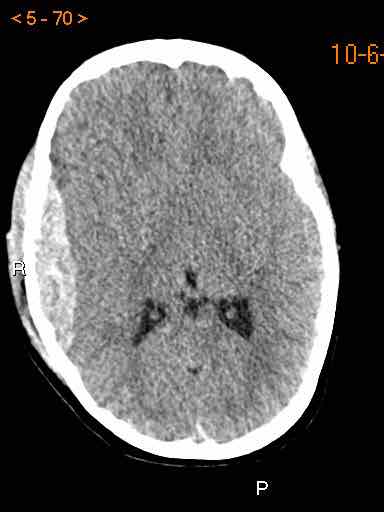

Tụ máu dưới màng cứng đồng tỷ trọng

Khi tụ máu dưới màng cứng tiến triển theo thời gian, tỷ trọng của khối tụ máu sẽ giảm dần và có thể tương đương với tỷ trọng của nhu mô não, khiến việc phát hiện tổn thương trở nên khó khăn.

Đây là trường hợp tụ máu dưới màng cứng đồng tỷ trọng rất khó phát hiện (các mũi tên).

Lưu ý rằng ở mức cắt cao hơn có tụ máu dưới màng cứng hai bên.